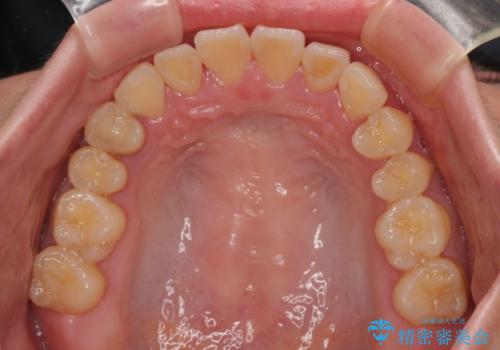

急速拡大装置 狭い歯列を拡大してクロスバイトを短期間矯正治療

- 1年4ヶ月

上顎の急速拡大装置を使用して上顎骨を側方に拡大することで上顎歯列を拡大し、下顎歯列も拡大できるようにすることで、歯列を整えることとしました。